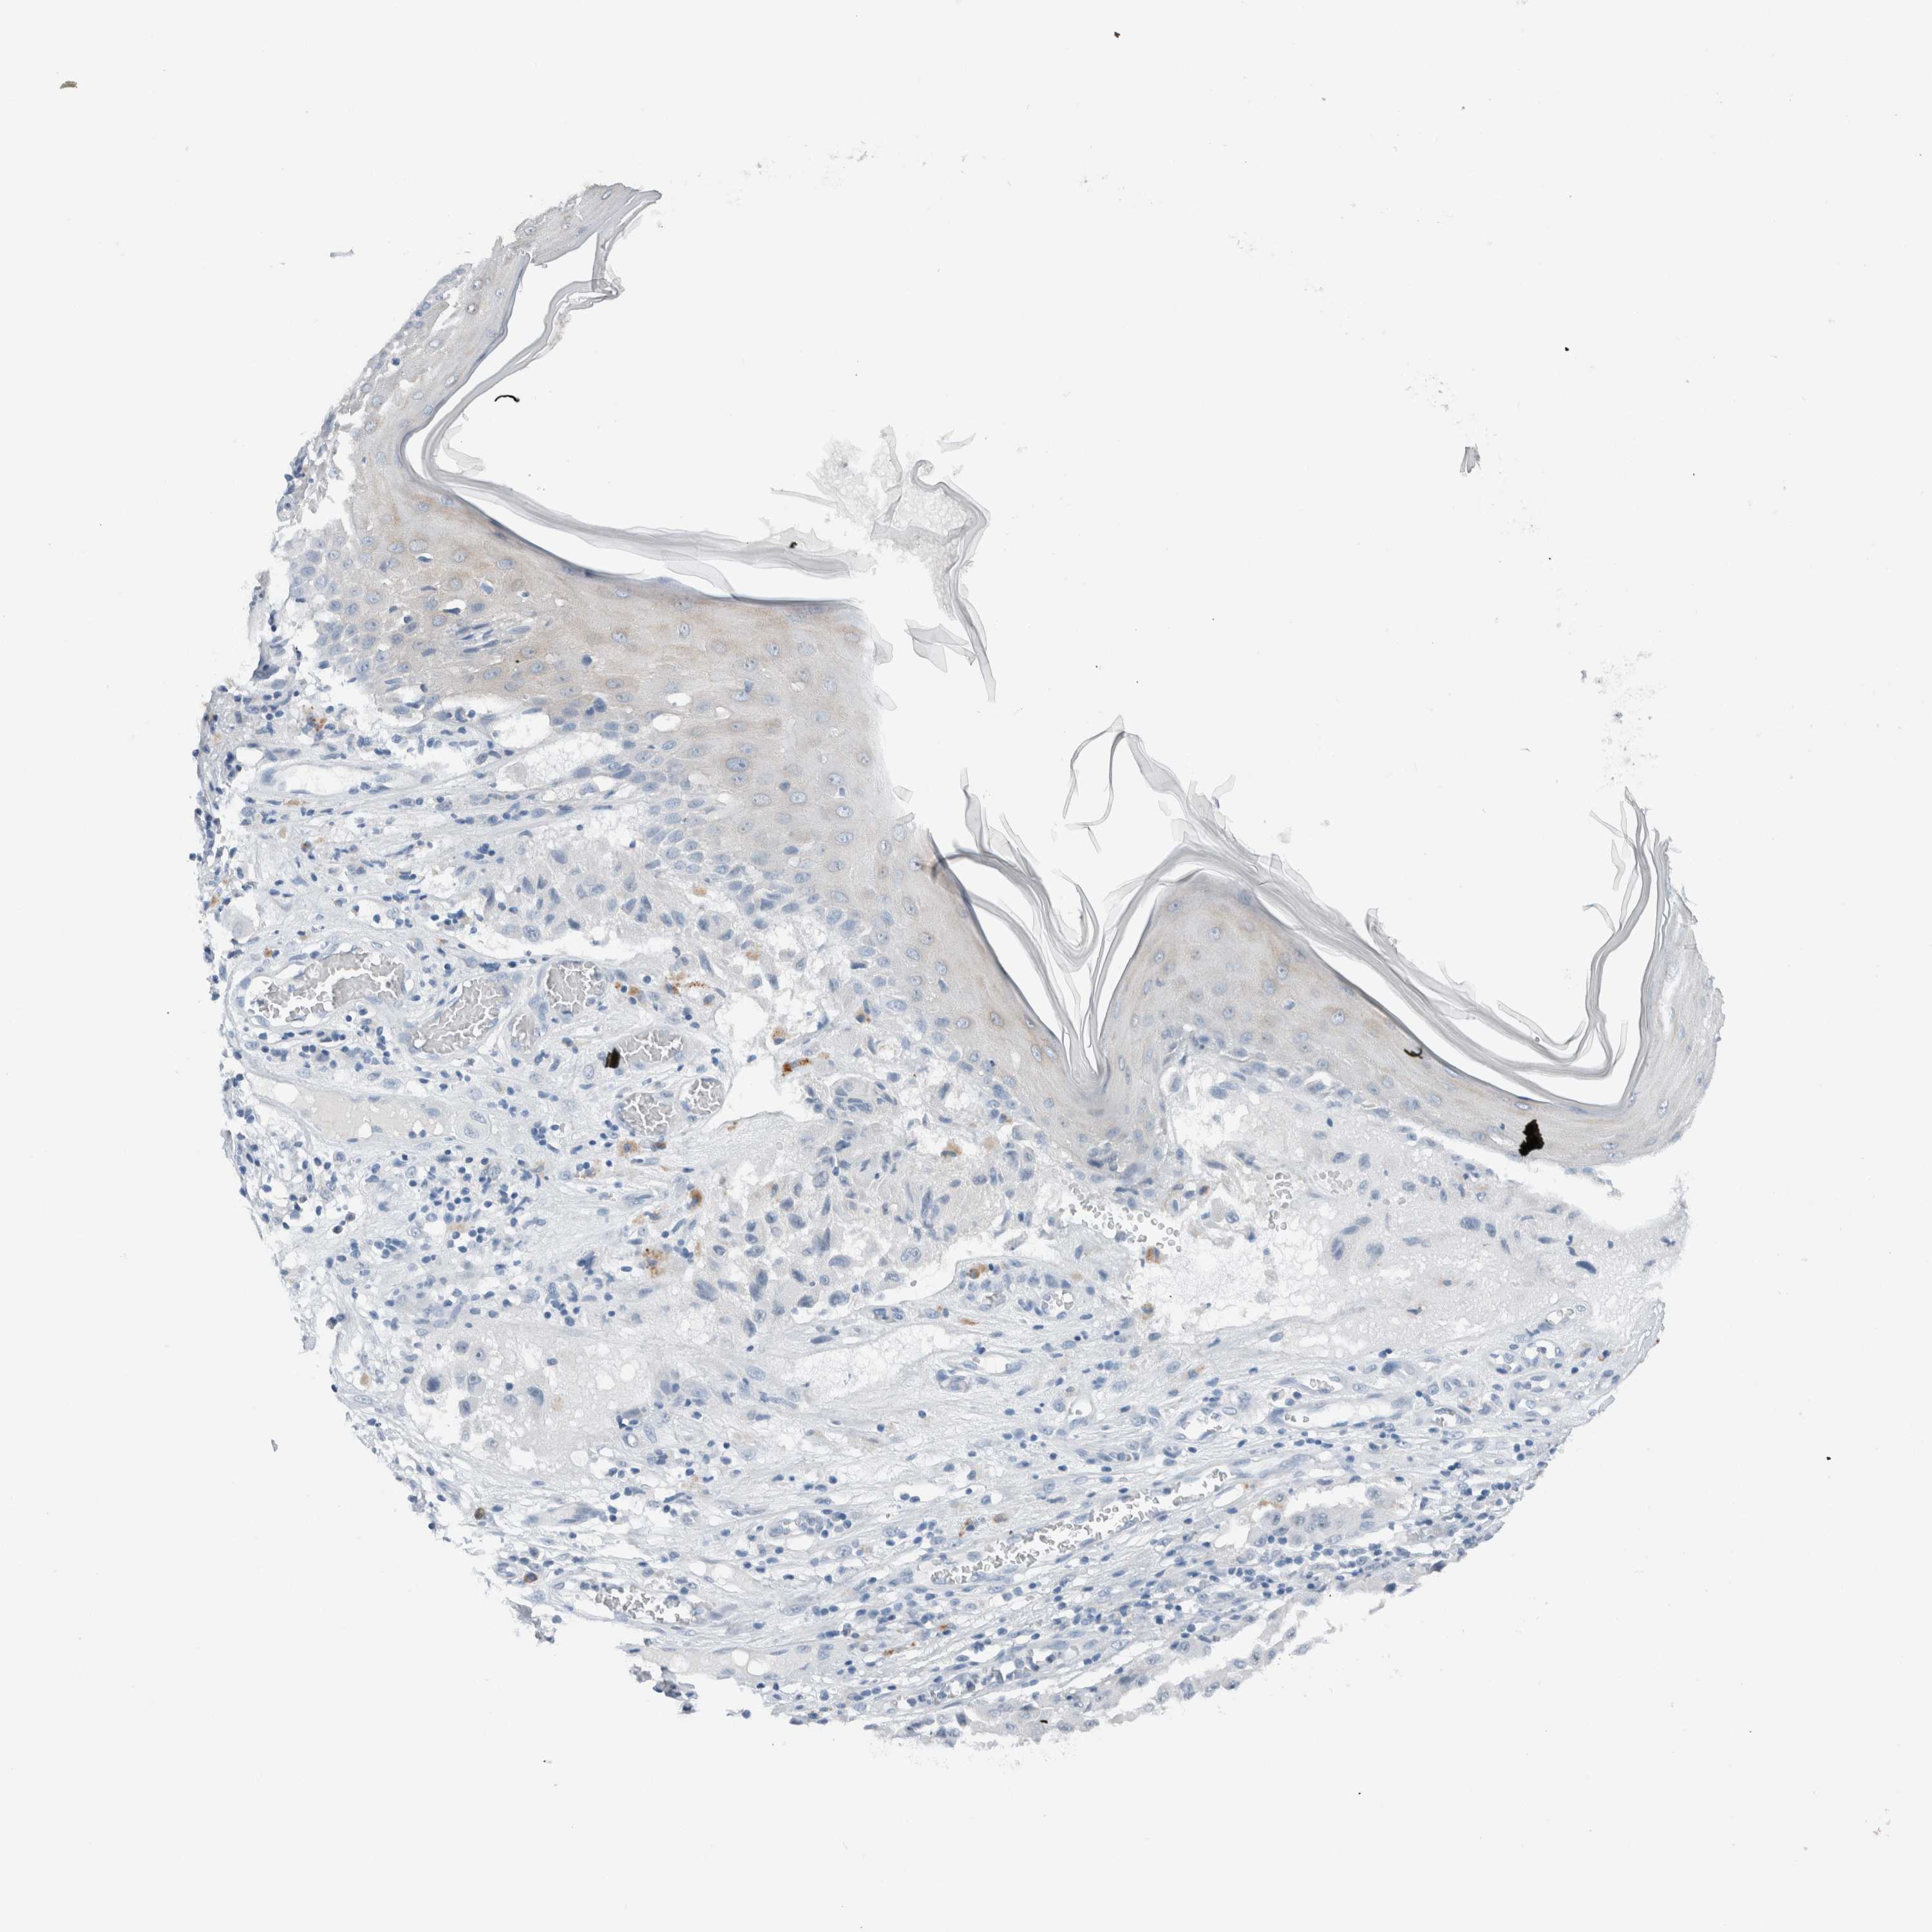

MELANOMA - Protein expressioni

A mouse-over function shows sample information and annotation data. Click on an image to view it in a full screen mode. Samples can be filtered based on level of antibody staining by selecting one or several of the following categories: high, medium, low and not detected. The assay and annotation is described here.

Note that samples used for immunohistochemistry by the Human Protein Atlas do not correspond to samples in the TCGA dataset.

Antibody stainingi

Antibody staining in the annotated cell types in the current human tissue is reported as not detected, low, medium, or high, based on conventional immunohistochemistry profiling in selected tissues. This score is based on the combination of the staining intensity and fraction of stained cells.

Each image is clickable and will lead to virtual microscopy that enables deeper exploration of all samples and also displays staining intensity scores, fraction scores and subcellular localization as well as patient and tissue information for each sample.

Antibody HPA023544

Staining

High

Medium

Low

Not detected

Intensity

Strong

Moderate

Weak

Negative

Quantity

>75%

75%-25%

<25%

None

Location

Nuclear

Cytoplasmic/membranous

Cytoplasmic/membranous,nuclear

Malignant melanoma, NOS

Malignant melanoma, Metastatic site